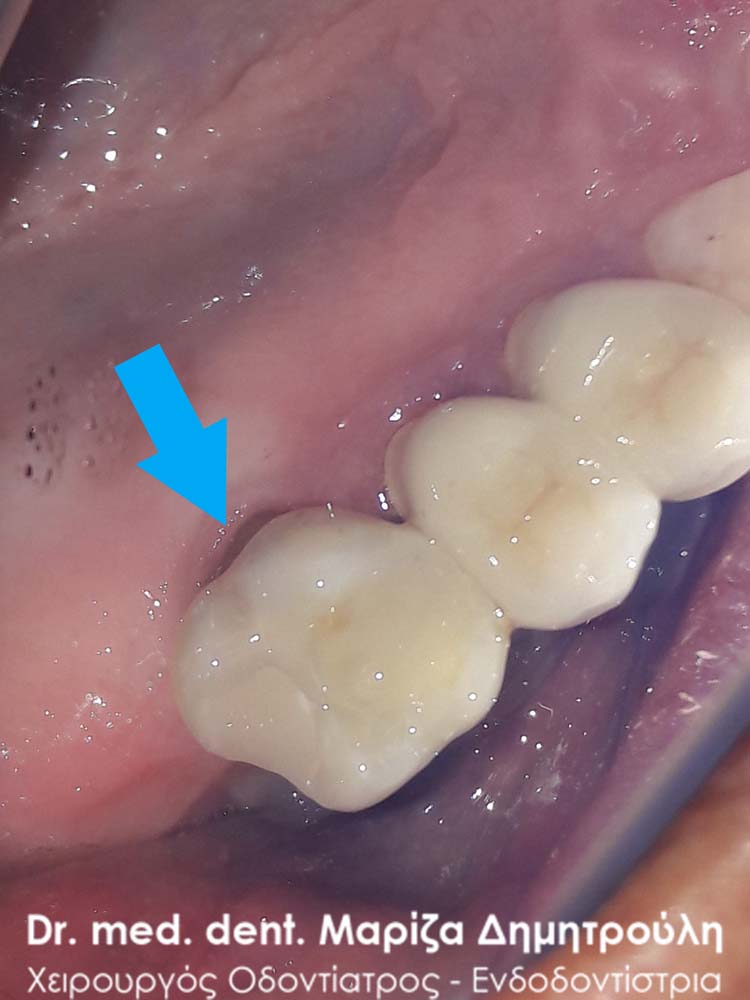

AFTER

Removal of amalgam (silver) filling

BEFORE

AFTER

AFTER